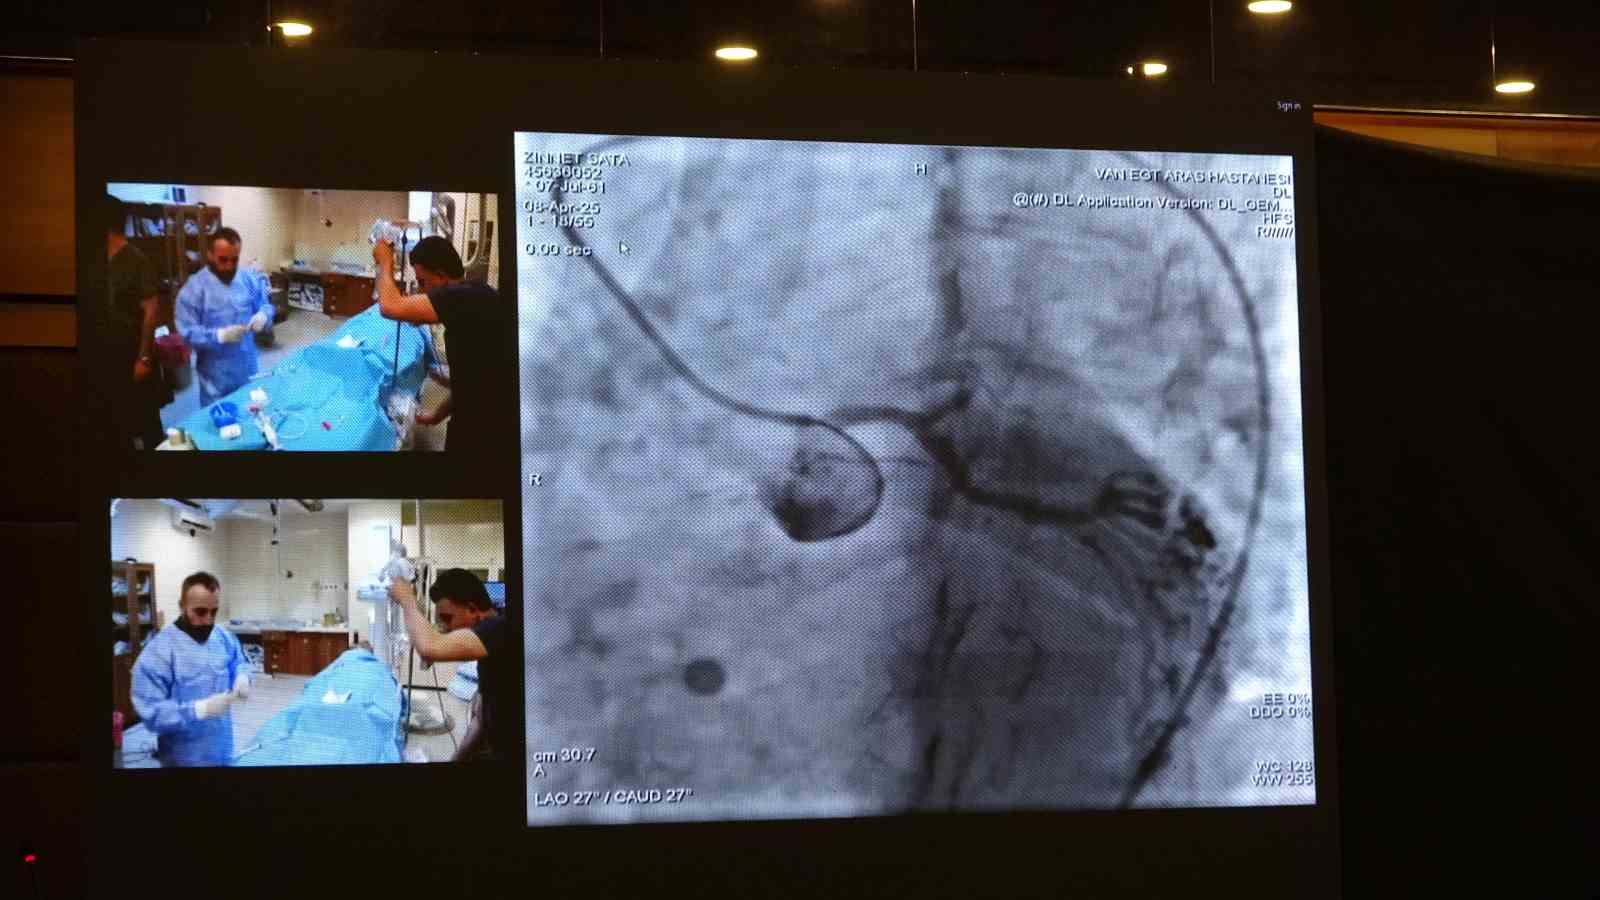

Türkiye’nin önemli kardiyoloji etkinliklerinden biri olan Girişimsel Kardiyovasküler Akademi 2025, bu yıl Van’da düzenlendi. Kardiyovasküler Akademi Derneği’nin öncülüğünde yapılan sempozyum, Van YYÜ ve Van Eğitim ve Araştırma Hastanesi Kardiyoloji Kliniği’nin ortak çabasıyla hayata geçirildi. Van Eğitim ve Araştırma Hastanesi’nin kateter laboratuvarlarında gerçekleştirilen 12 canlı vaka oturumunda; sol ana koroner müdahaleleri, bifurkasyon ve kompleks PFO/ASD vakaları, tam tıkalı damar (CTO) işlemleri, karotis, EVAR, TAVI, apendiks kapama, septal ablasyon ve mitral balon valvüloplasti gibi işlemler başarıyla uygulandı.

Hastanede gerçekleştirilen canlı vaka işlemlerinin Türkiye’deki tüm kardiyologlar tarafından izlenebildiğini belirten Van Eğitim ve Araştırma Hastanesi Başhekimi Doç. Dr. Remzi Sarıkaya ise "Bu bizim için son derece önemli bir adım. Gerçekleştirilen vakaların tamamı oldukça zorlu vakalar olup, geçmişte bu tür işlemler bu bölgede yapılmazken, son dönemde hem ilimizde ciddi bir şekilde yapılmaya başlanmış hem de tecrübe aktarımı noktasında önemli bir aşama kaydedilmiştir. Tüm ekip arkadaşlarımı bu başarılarından dolayı kutluyorum. Peki, bu canlı vakalar nelerdir? Ameliyatsız aort kapak değişimi, kalp deliklerinin kapatılması, daha önce tek seçenek olarak ameliyatla tedavi edilen ciddi ana koroner lezyonları ve çatallanma olarak adlandırılan bifurkasyon stentlemeler, sol atriyal apendiks kapama dediğimiz pıhtı atan deliklerin kapatılması, aort damarda var olan anevrizmaların kapatılması gibi son derece zor ve karmaşık vakalar burada canlı yayında gerçekleştirilerek tecrübe aktarımına imkan sağlamaktadır. Bu tür bir toplantının ilimizde yapılması ve bu tecrübe aktarımının gerçekleştirilmesi bizim için büyük bir gurur kaynağıdır" diye konuştu.